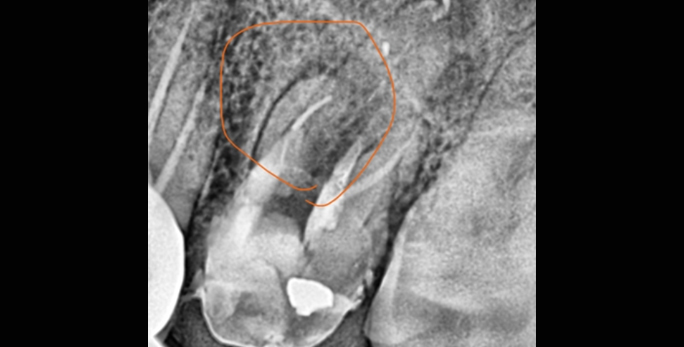

• 타원신경치료 실패 후 발치평가 받은 환자 치근단 절제술로 발치하지 않고 부러진 기구 제거 및 치아 보존